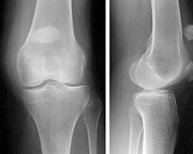

La articulación de la rodilla está formada por las partes inferior del fémur, superior de la tibia y posterior de la rótula actuando como una gran bisagra. Es la articulación más lesionada en el deportista y su tratamiento exige un gran conocimiento de la anatomía así como de la cirugía traumatológica, protésica y artroscópica.

Fracturas del tercio superior de la tibia

Las fracturas en el tercio superior de la tibia suponen el 1% de todas las fracturas y el 8% de las fracturas del anciano. Están causadas por fuerzas violentas que producen desviaciones laterales sobre la rodilla. La osteoporosis en el paciente de edad facilita estas fracturas. Son lesiones que también vemos en el ámbito deportivo fundamentalmente en aquellos deportes que exigen un sobreesfuerzo de la articulación de la rodilla como el esquí, el fútbol o el patinaje. En los deportistas suelen acompañarse, además, de lesiones ligamentosas que pueden pasar desapercibidas si no se realiza una exploración exhaustiva.

El tratamiento de las fracturas del tercio superior de tibia es quirúrgico con la finalidad de devolver a la rodilla su anatomía normal para el rápido inicio de la movilidad articular. Los avances en técnica artroscópica y los nuevos implantes permiten el tratamiento de estas fracturas de una forma poco agresiva y fiable que disminuye las complicaciones postoperatorias y agiliza el tiempo de recuperación.

Fracturas de rótula

Las fracturas de rótula representan el 1% de todas las fracturas del esqueleto. Son doblemente más frecuentes en la mujer que en el hombre y, sobre todo, entre la tercera y quinta década de la vida. El impactode la rodilla en flexión sobre el suelo suele ser el mecanismo de producción habitual aunque en otras ocasiones se debe a una contracción brusca del cuádriceps. El hematoma y la imposibilidad para mover la rodilla hacen sospechar el diagnóstico que se confirma radiológicamente con una proyección lateral. El tratamiento de las fracturas de rótula se ha beneficiado de los avances en traumatología mínimamente invasiva pudiendo ser resueltas a través de pequeñas incisiones en la piel gracias a la ayuda de la artroscopia.